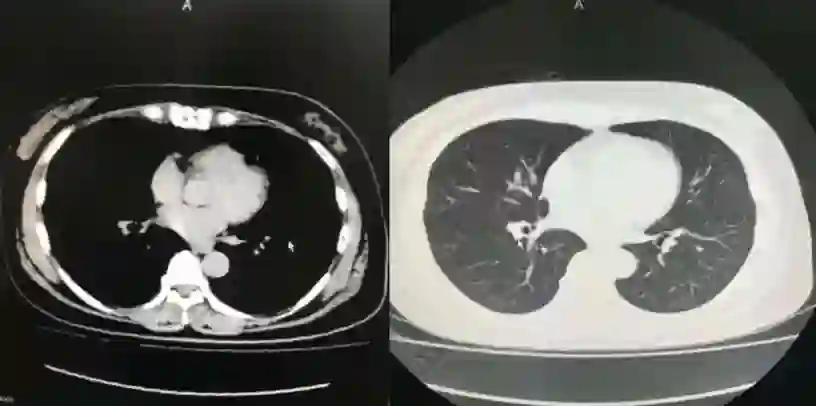

2008年10月7日ECT检查结果

2008年10月7日CT检查结果